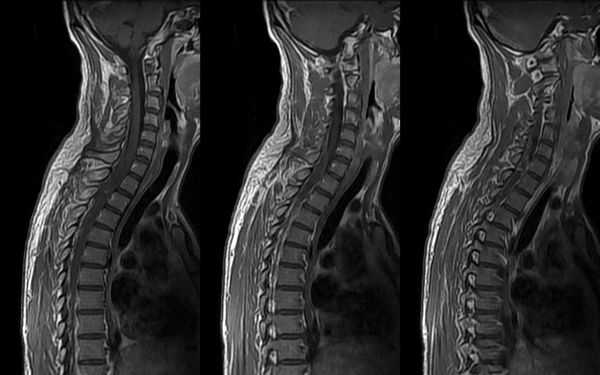

Рентгенограмма, МРТ искусственного шейного межпозвонкового диска